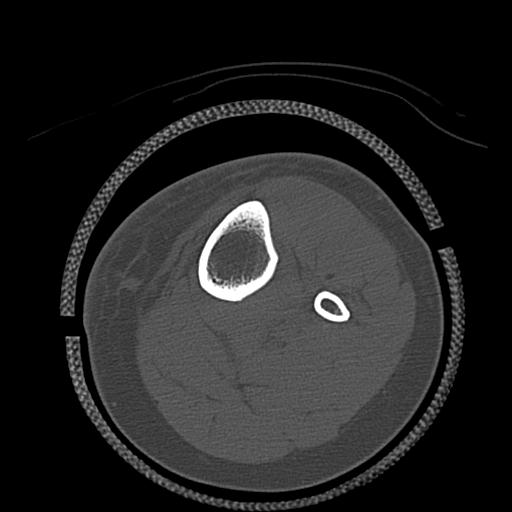

49554 3/13 膝 4R 3/16 4R 1/18 2R 78歳男性 膝蓋骨骨折